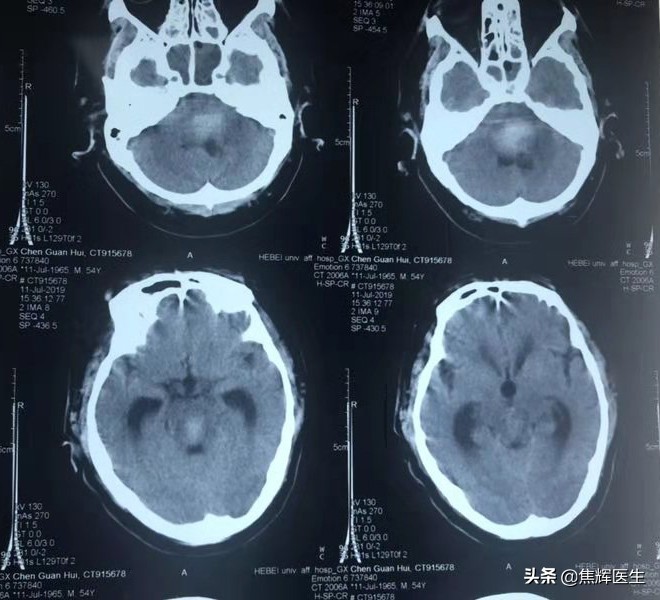

患者陈某某,男性,54岁,于2019年6月22日晚8点在家昏迷,当地医院诊断脑干出血。

患者儿子7月27日到北京天坛普华医院找到我,我建议做穿刺后微创分流术,因为患者在当地医院穿刺三次,脑压超过正常范围250~300毫米水柱,我认为脑干出血的患者脑压高,脑水肿持续时间很长,不是过去认为经过脱水治疗可以把脑压暂时降低,另外很多人学术上认为昏迷患者脑水肿靠自己吸收是可以的,但是我认为昏迷患者脑水肿即便自己吸收,是相当慢的过程,一延误就是几个月过去了,脑室扩大不说,还不容易苏醒,我经过临床研究发现,早期穿刺减压可以快速降低脑水肿,患者清醒较快。但是清醒后颅内压不是恒定不变的,它会不断的动态变化,如果脑压不稳,二次出血、三次出血就会发生,严重威胁患者的生命和生活质量,还会给患者及家属带来精神紧张情绪,总怕再次出血。